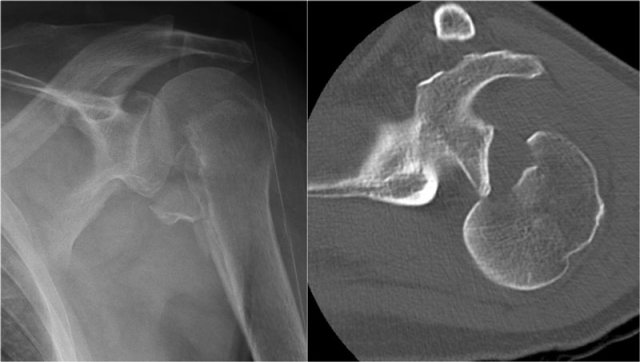

Osseus Bankart

Bankart lesions with an osseus fragment are common findings in patients with an anterior dislocation and are frequently seen on the x-rays or CT-scan.

On MR-arthrography it may be difficult to depict the osseus fragment.

On CT it is easy to appreciate the osseus fragment of the anterior glenoid (arrow).

Reverse Bankart

CT-images in another patient show a reversed osseus Bankart in a patient with posterior dislocation.